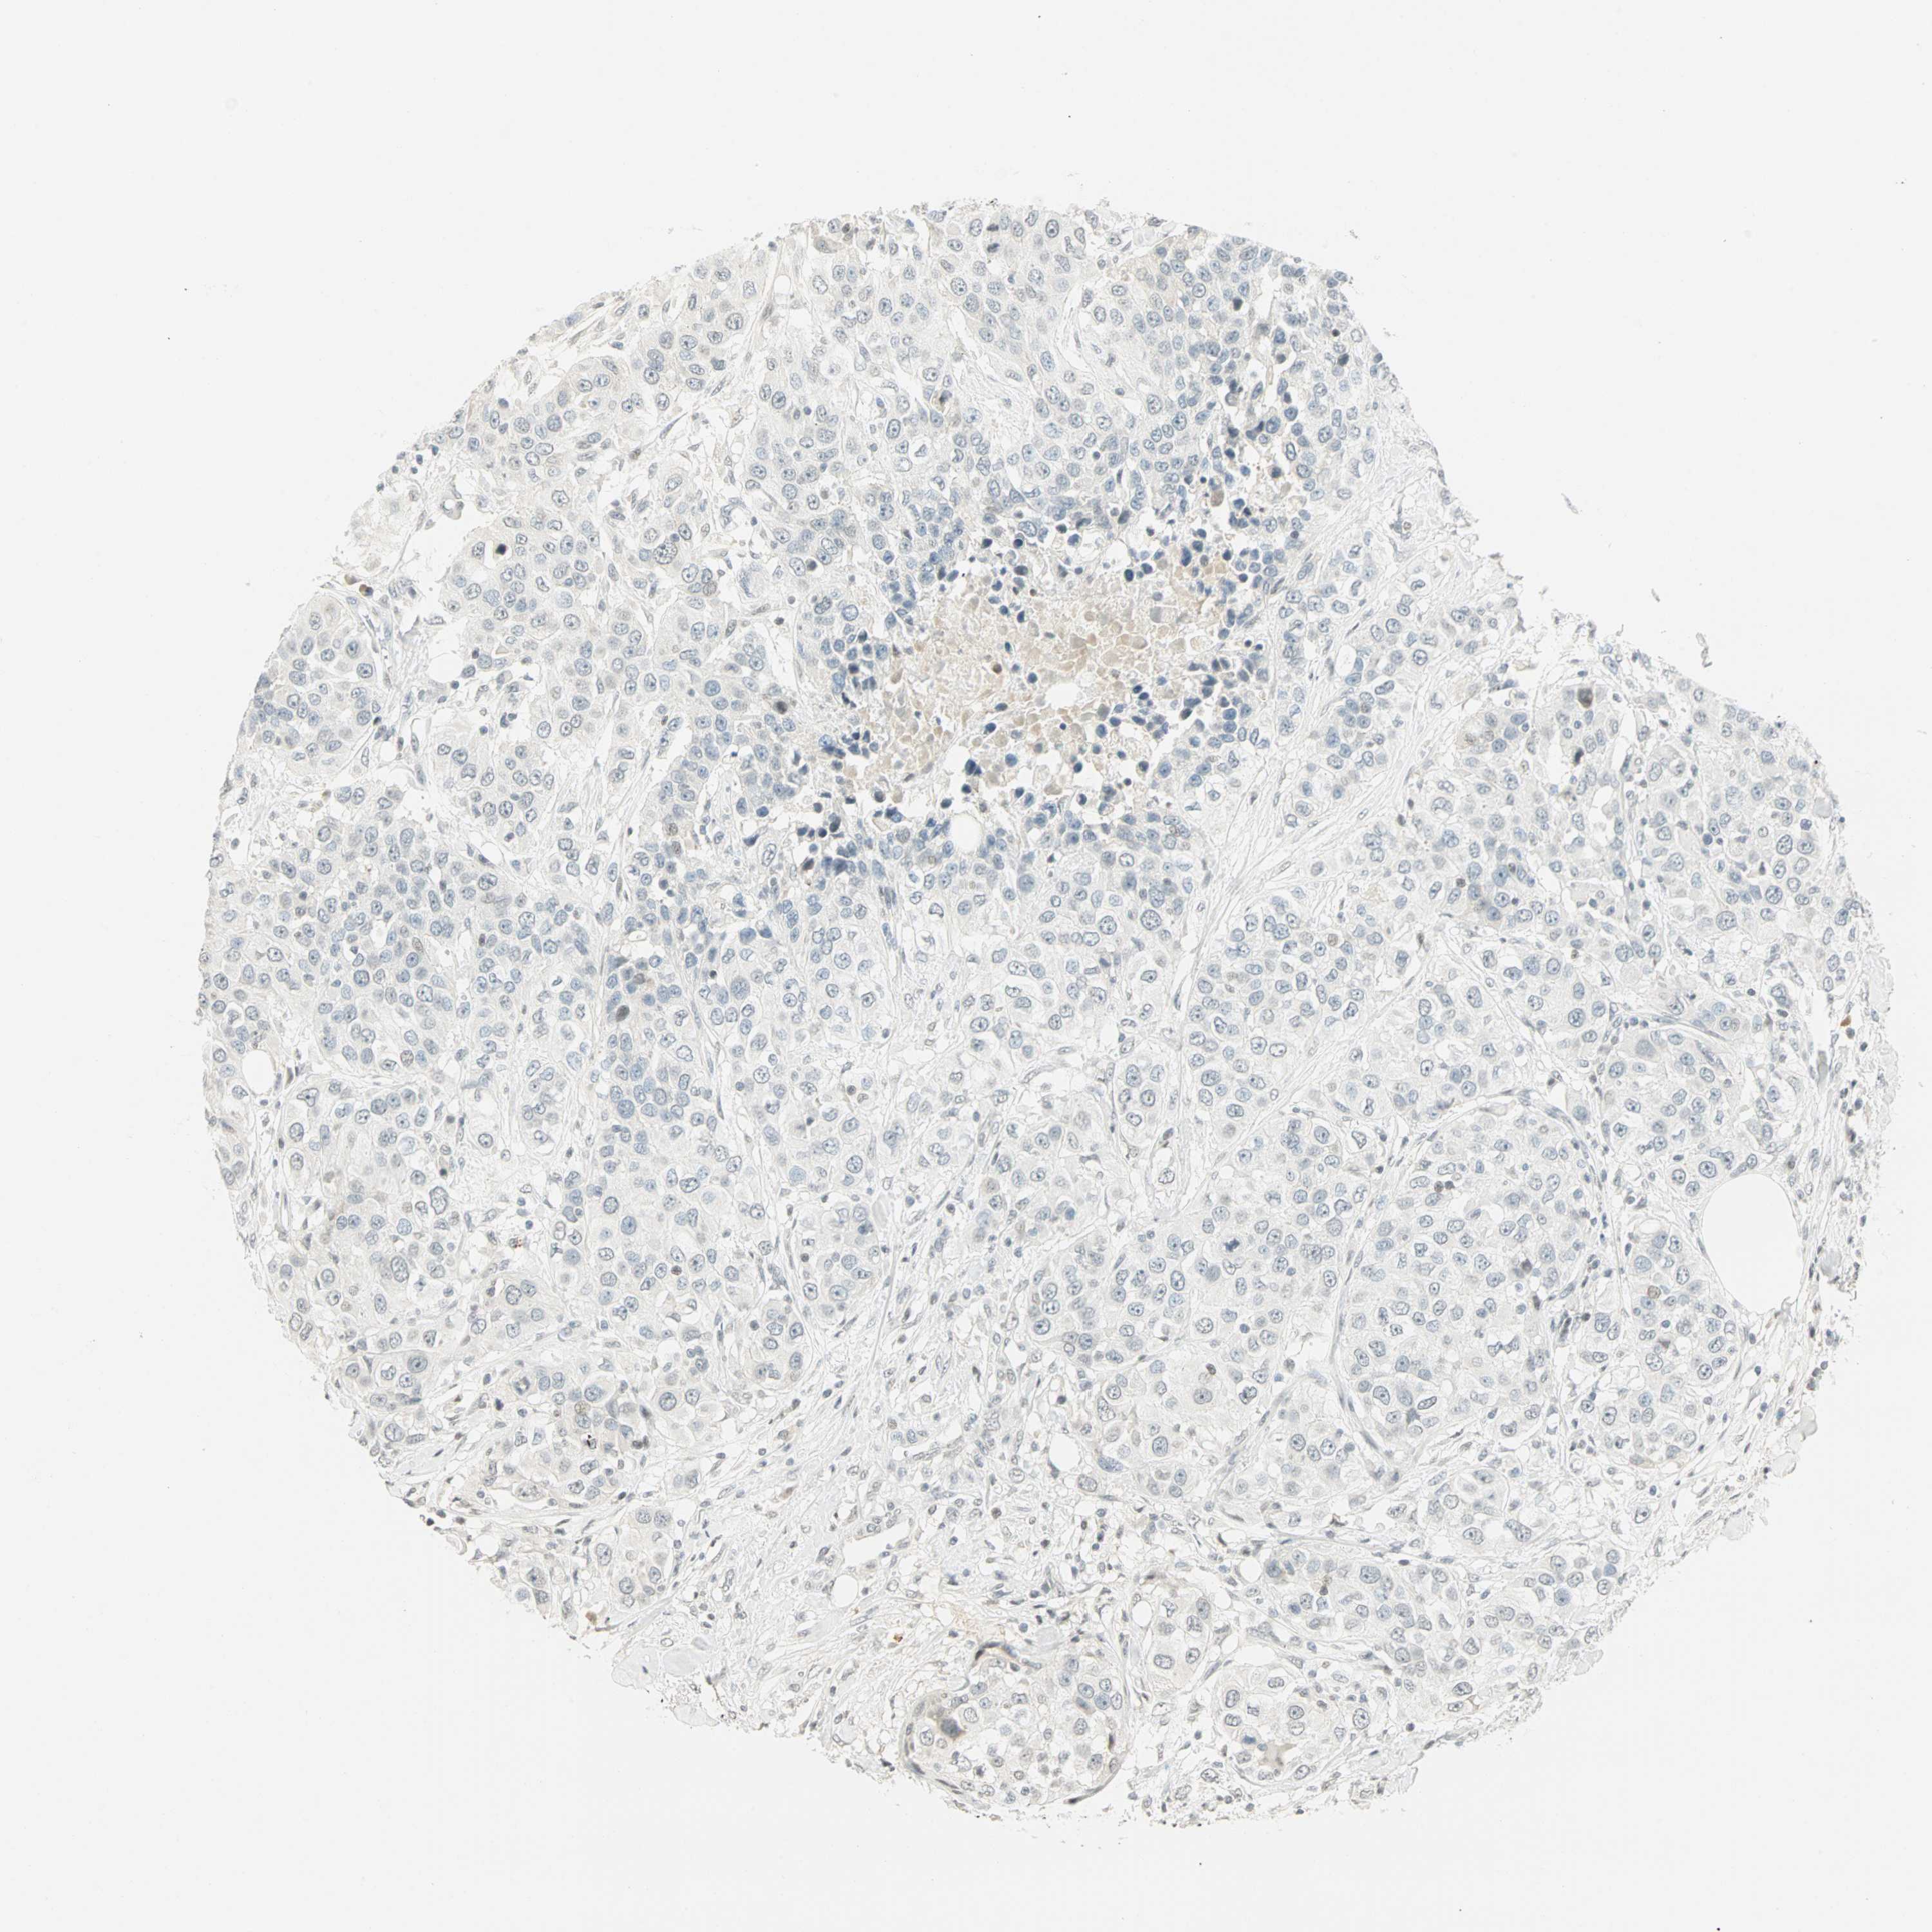

UROTHELIAL CANCER - Protein expressioni

A mouse-over function shows sample information and annotation data. Click on an image to view it in a full screen mode. Samples can be filtered based on level of antibody staining by selecting one or several of the following categories: high, medium, low and not detected. The assay and annotation is described here.

Note that samples used for immunohistochemistry by the Human Protein Atlas do not correspond to samples in the TCGA dataset.

Antibody stainingi

Antibody staining in the annotated cell types in the current human tissue is reported as not detected, low, medium, or high, based on conventional immunohistochemistry profiling in selected tissues. This score is based on the combination of the staining intensity and fraction of stained cells.

Each image is clickable and will lead to virtual microscopy that enables deeper exploration of all samples and also displays staining intensity scores, fraction scores and subcellular localization as well as patient and tissue information for each sample.

Antibody HPA067203

Antibody CAB008094

Antibody CAB069409

Staining

High

Medium

Low

Not detected

Intensity

Strong

Moderate

Weak

Negative

Quantity

>75%

75%-25%

<25%

None

Location

Nuclear

Cytoplasmic/membranous

Cytoplasmic/membranous,nuclear

Urothelial carcinoma, High grade

Urothelial carcinoma, NOS

Urothelial carcinoma, Low grade